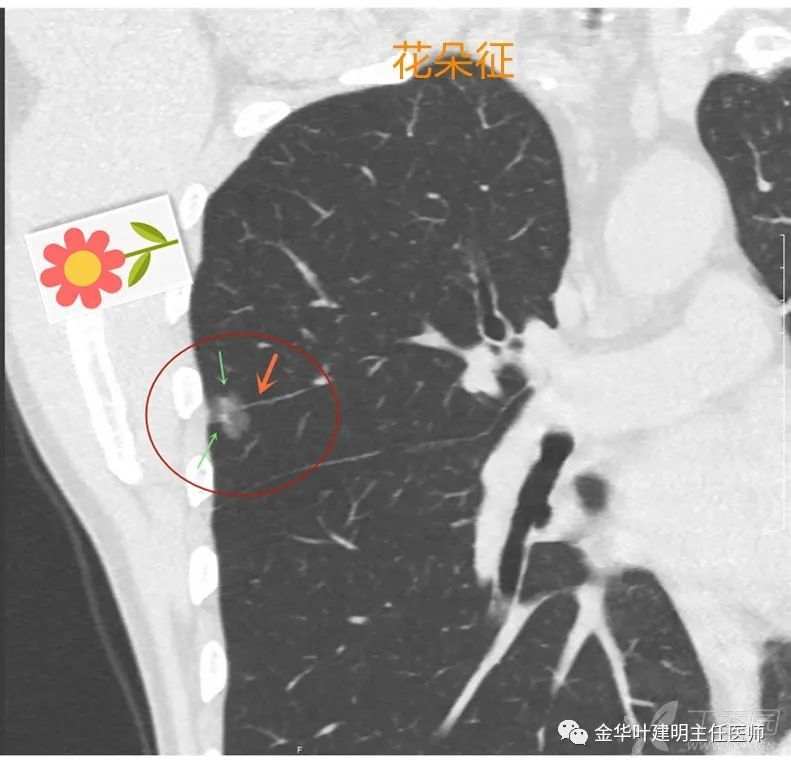

花朵征

花朵征:病灶有浅分叶的前提下,又有血管进入,其实是浅分叶与血管征的综合,看着就像一朵花,血管就是花的枝。若是病灶缺乏分叶征,是圆形的,则像棒棒糖。